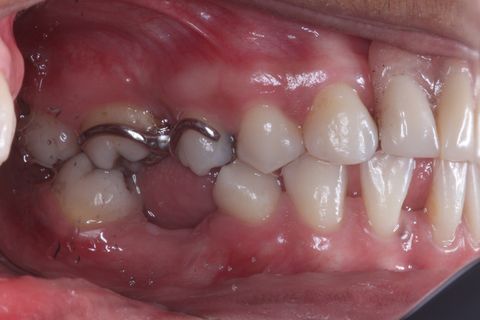

Foto Inicial. Paciente fazendo uso de Prótese Parcial removível.

Foto Perfil (uso de espelho). Lado esquerdo

Foto Perfil (uso de espelho). Lado Direito